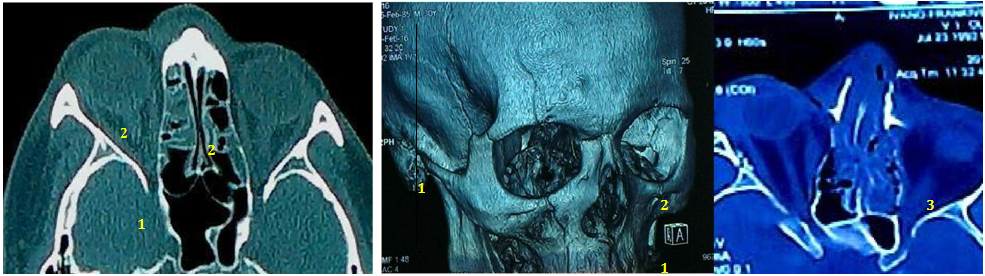

Patients F and L (Figure 2) were in better general condition. The damage of the orbital bones in the apex with retrobulbar hematoma appeared in the early stages. They had blurring of vision and bilateral central scotomas. They received the same steroid neuroprotection as patient B. Their visual acuity became better (0.8 in affected side and 1.0 in opposite) in four months. The question of surgical treatment remains open under lesions in the top area of the orbit, a possible high risk of injury to the optic nerve. One more patient S started his treatment from Methylprednisolone in dose 1000 mg. He took Phosphine-stimulation after two weeks. His examination after the first four months showed that his visual acuity on the right (affected) eye increased from 0.4 to 0.8. On the left side (opposite), visual acuity has become better also, from 0.8 to 1.0. However, his eye movement is limited. He had double vision, corrected by prism lens. Therefore, given the high risk of re-injury of the optic nerve, the issue of plastic orbit remains currently open.

Figure 2 CT scan of patient F. and L. (the last): the right orbital multiple bones fractures with apex dislocation (1), bilateral optic nerve swelling (2) and left retro bulbar hematoma (3). The damage of the orbital bones in the apex with retrobulbar hematoma appeared in the early stages. They had blurring of vision and bilateral central scotomas. Their visual acuity after treatment became better (0.8 in affected side and 1.0 in opposite) in four months. The question of surgical treatment remains open under lesions in the top area of the orbit, a possible high risk of injury to the optic nerve.